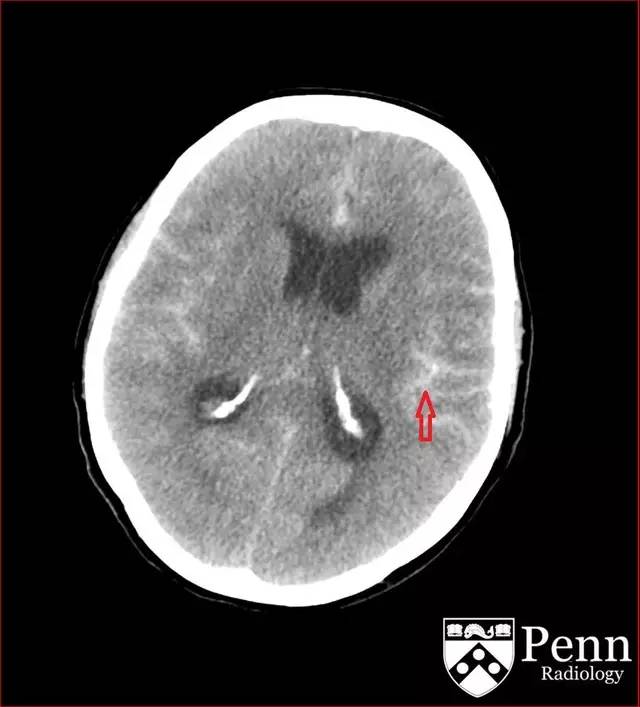

图 3 平扫 CT 蛛网膜下腔出血延伸到额叶(红色箭头)

CT 可见广泛的蛛网膜下腔出血,累及基底池、外侧裂并延伸到额叶。